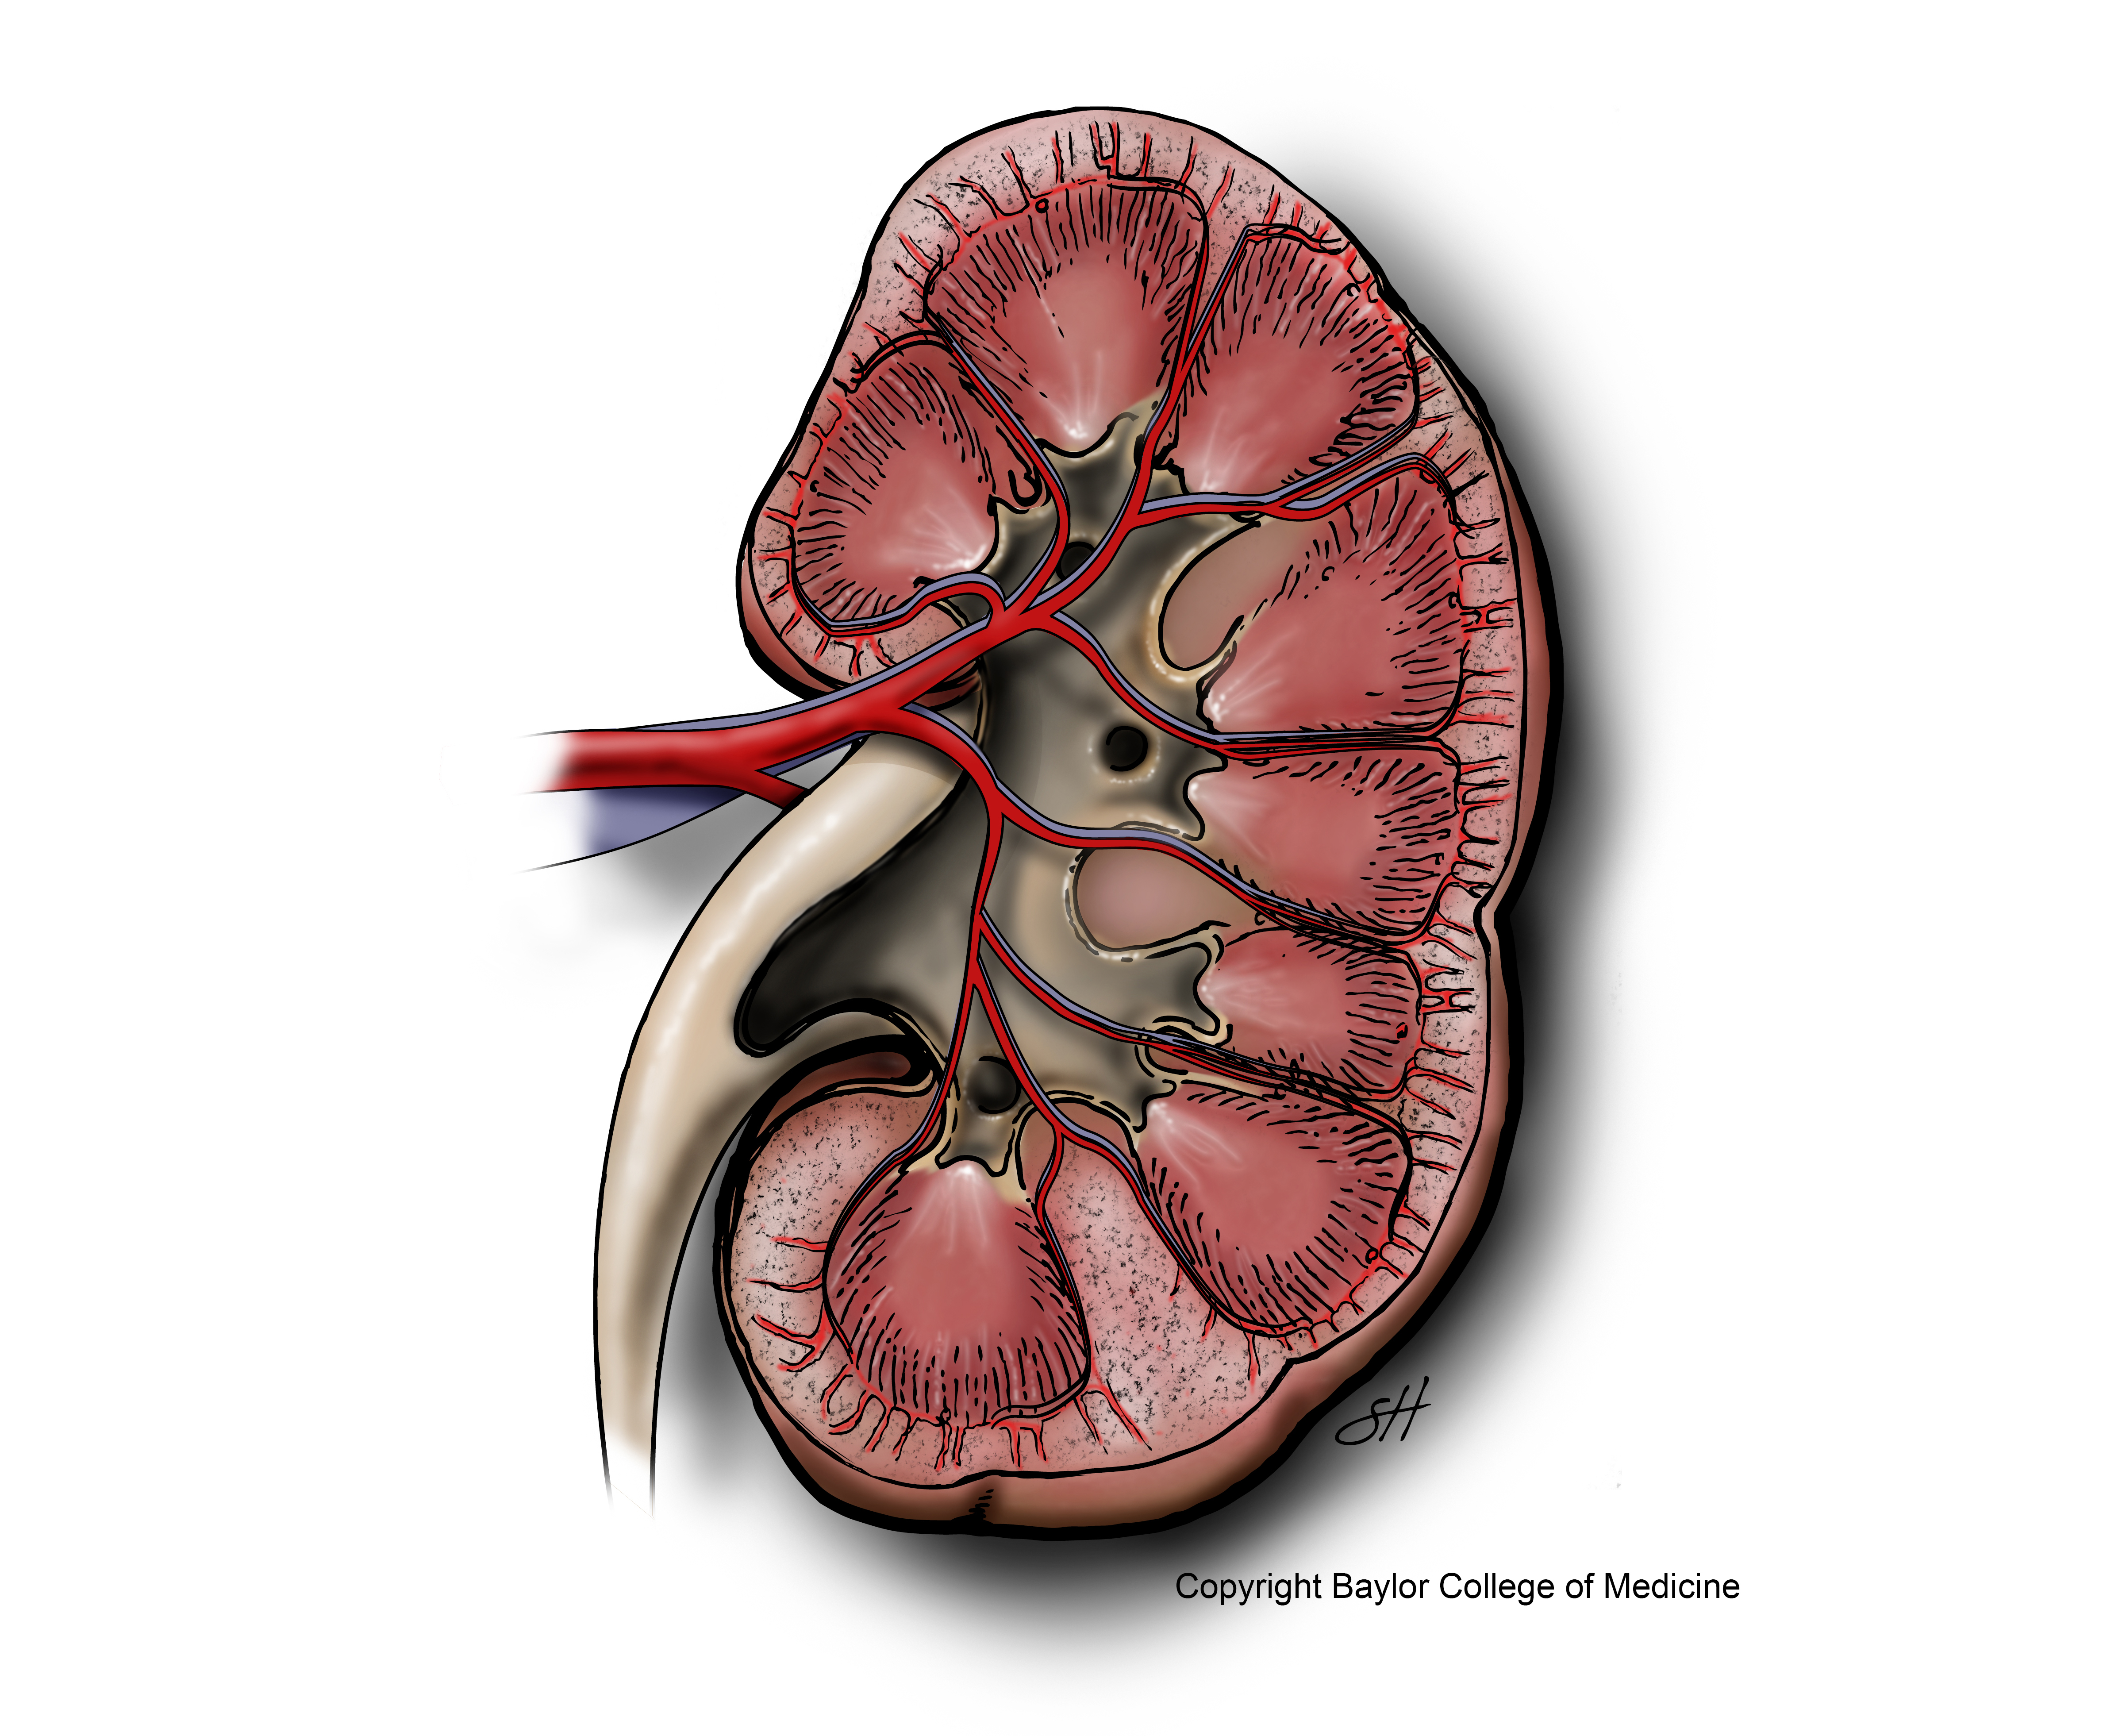

Nephrology

Molecular mechanisms of muscle wasting in uremia and other catabolic conditions; pathogenesis of diabetic nephropathy; cytokine-induced kidney disease; inflammatory mechanisms of glomerulonephritis; and strategies for treating progressive chronic kidney diseases